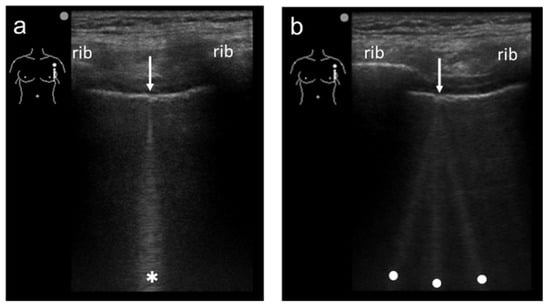

3.1. Spatial Compound Imaging